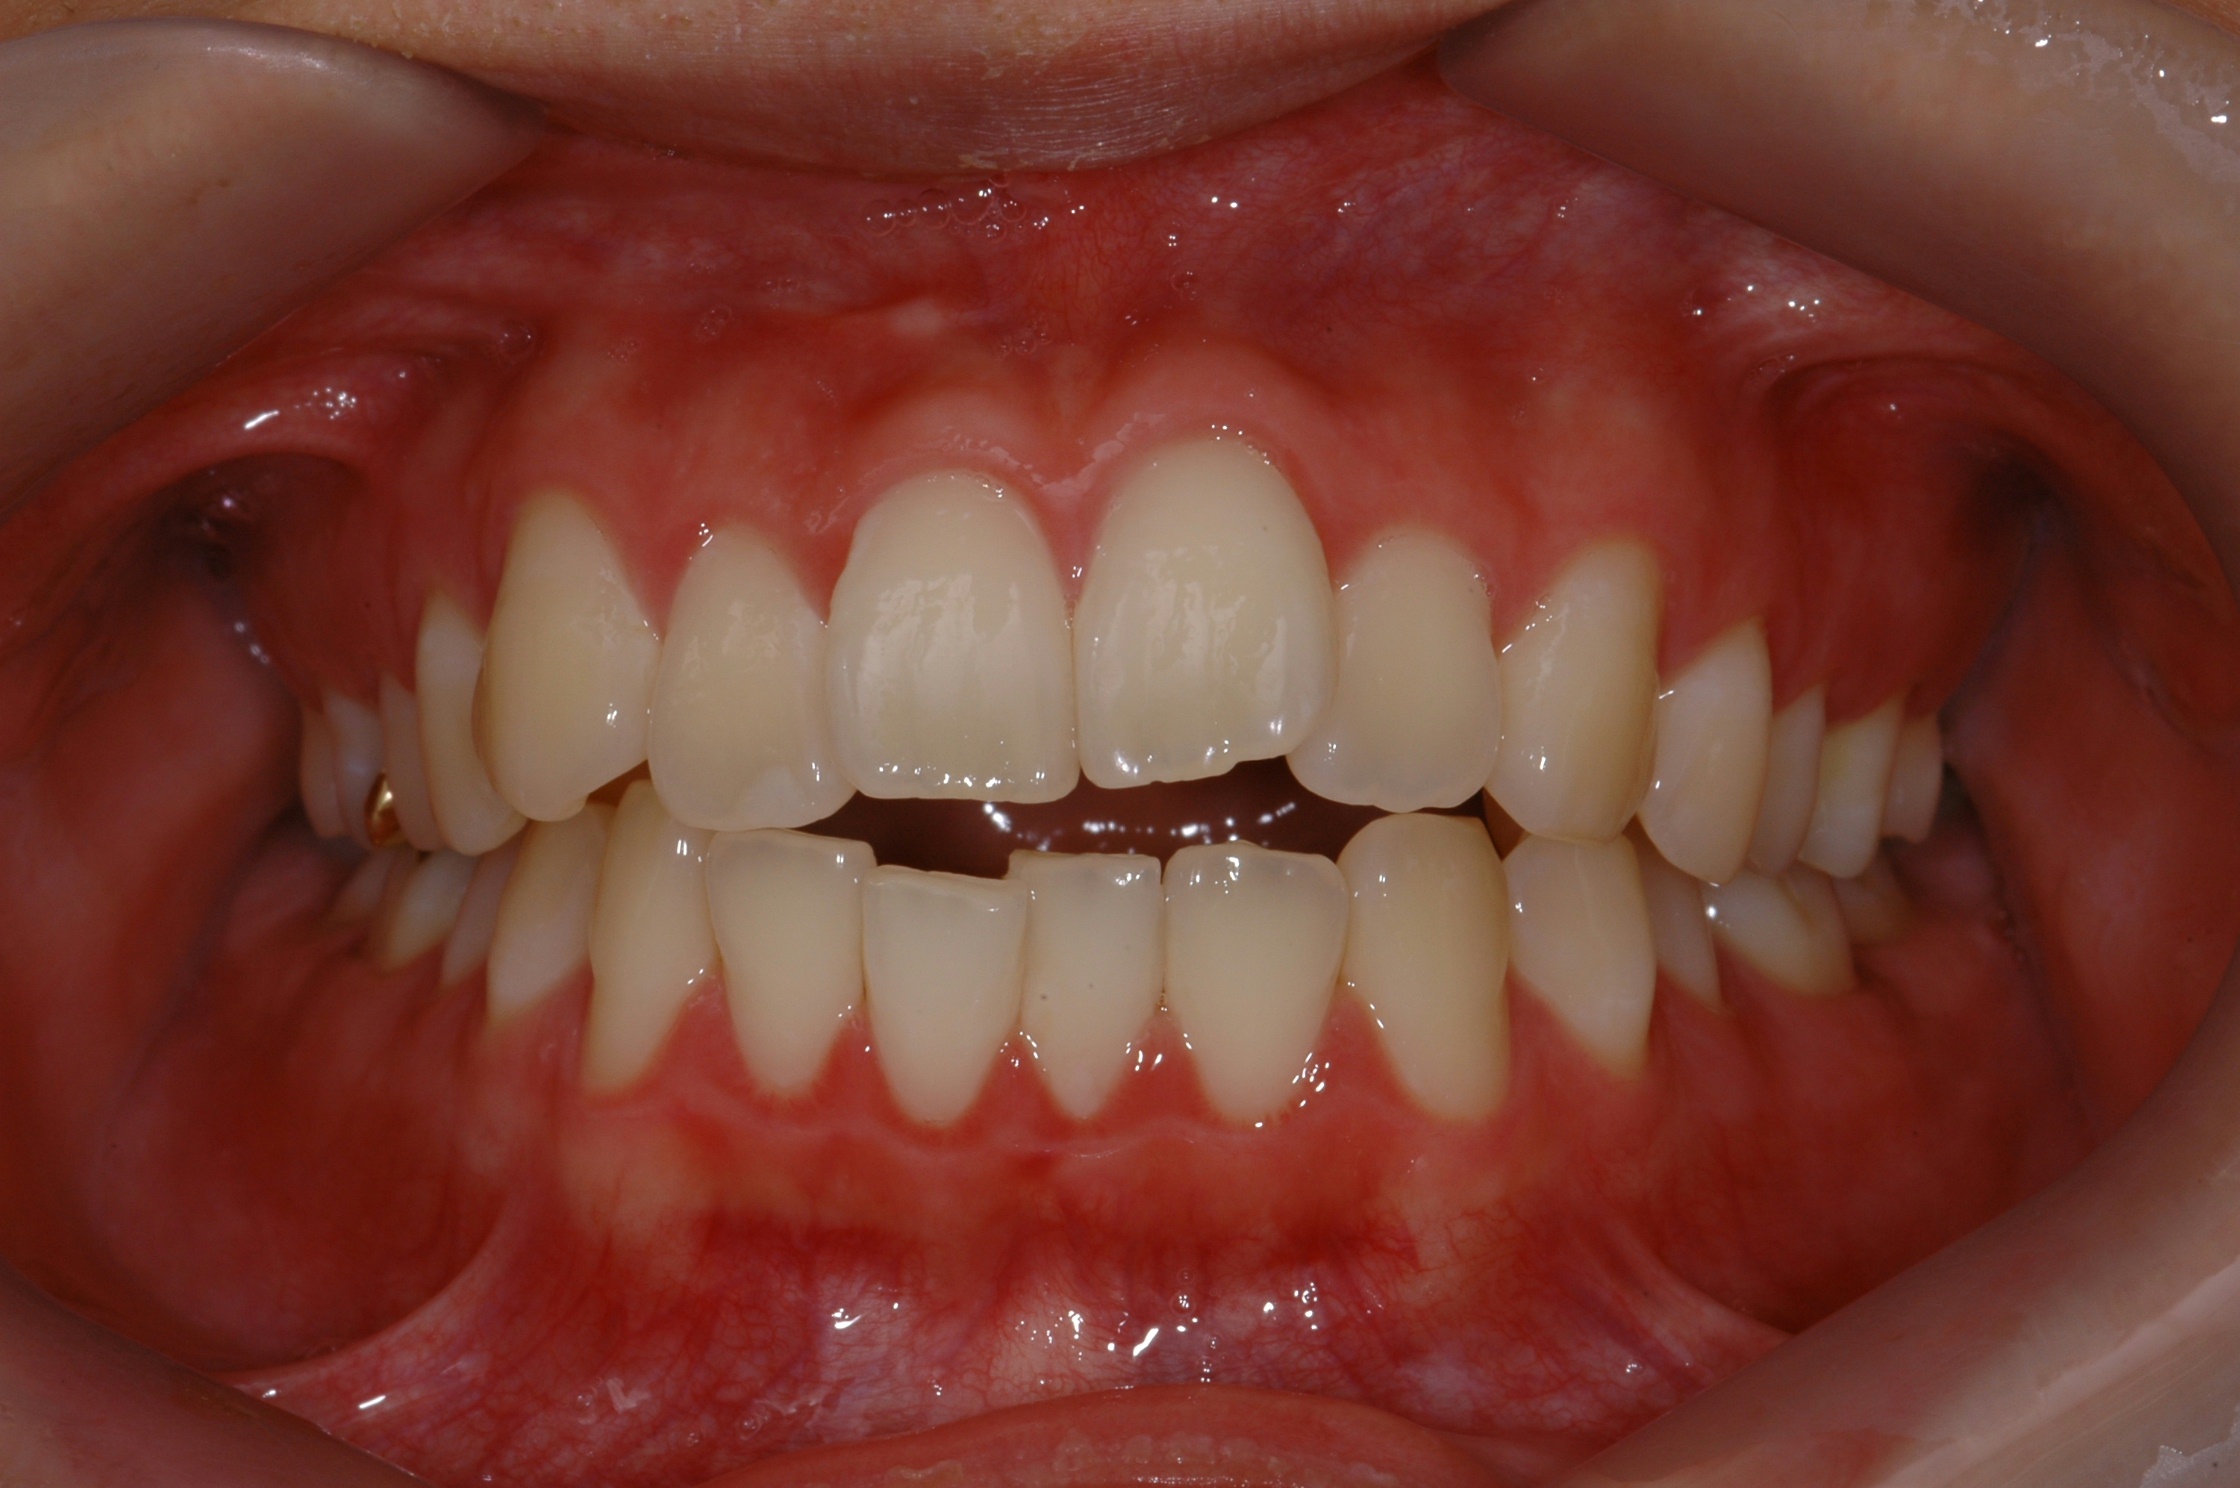

치료 전 사진입니다.